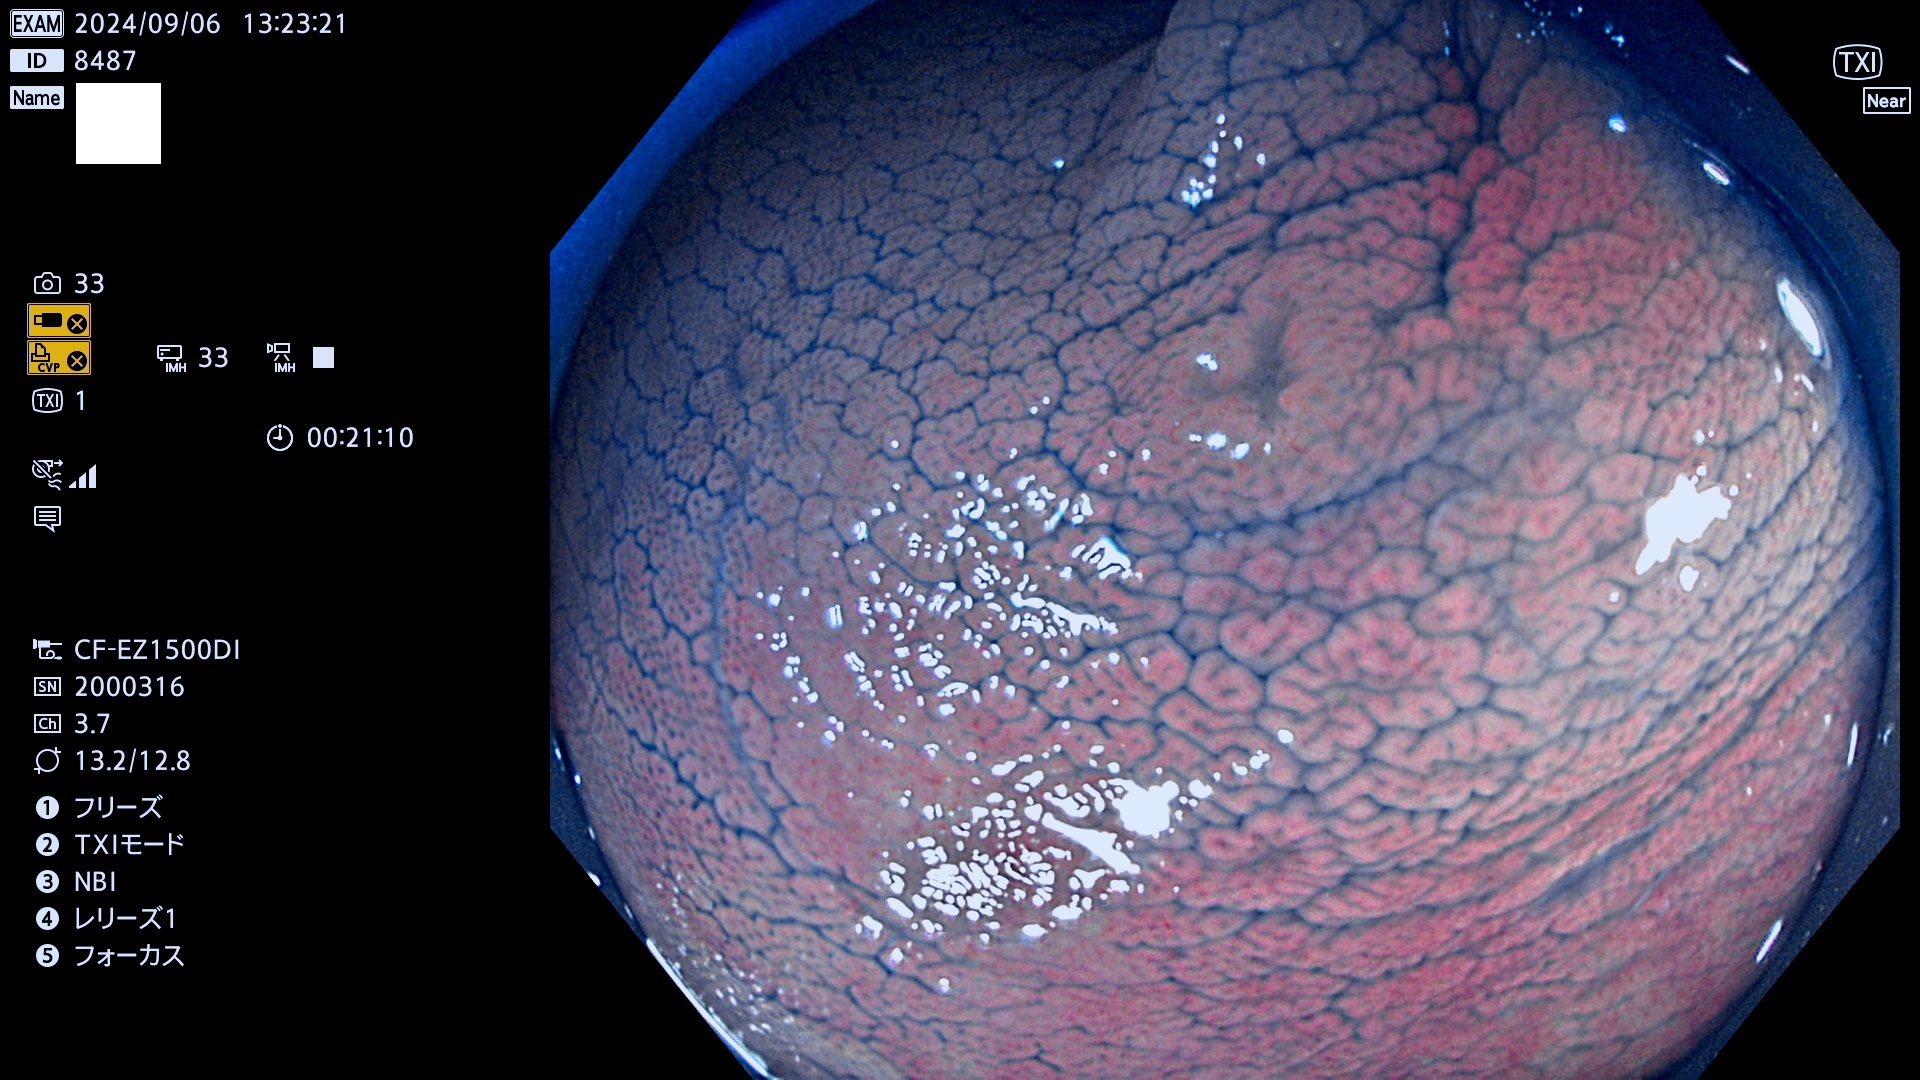

完全に平坦な物をUb、陥凹している物をUcと呼びます。最も発見が難しく危険な病変です。

抽出の対象期間 2024年9月5日〜9月8日の4日間(40件の検査)4件 (4/40=10%)